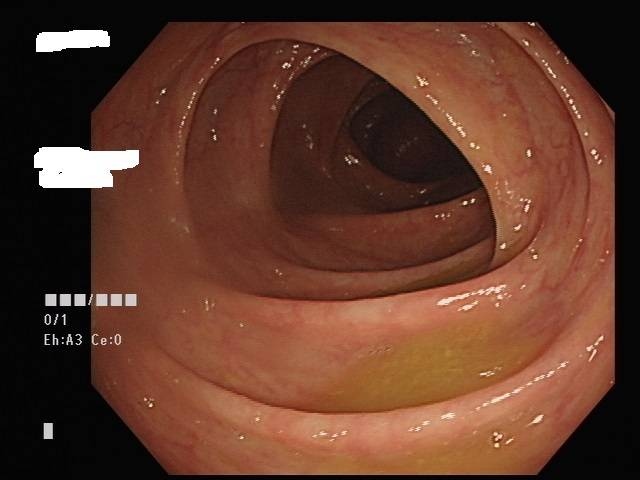

大腸鏡是一條黑色管子,由肛門進入依著大腸的走向,由下而上檢查:肛門→直腸→乙狀結腸→降結腸→橫結腸→升結腸。可以觀察整個大腸的任何病變,如:潰瘍、發炎、息肉、腫瘤及出血源,以進一步治療處置,如:息肉切除、切片、電燒止血等。

絕大部分的大腸息肉甚至是非常早期的大腸癌是可以用大腸鏡切除的,並不需要開刀。再將病灶送病理科切片檢查,將切片染色來判定是否為大腸癌,但大約都會需要2-3週的時間。大腸鏡檢查是動態的過程,在內視鏡於大腸內不斷往前推進的同時,有些息肉並不明顯,醫師是否能辨別每一個腸壁黏膜上的病灶,非常倚賴大腸鏡操作經驗和技術。